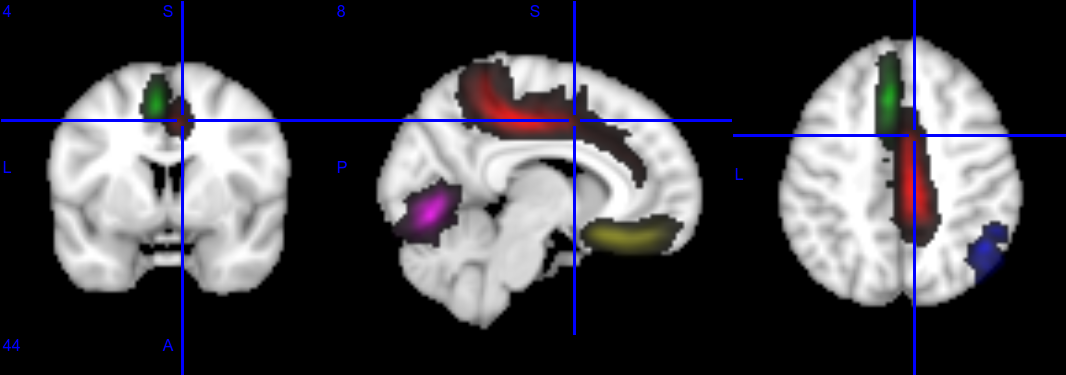

Probability maps¶

Probability maps corresponding to a few anatomical landmarks (cortical folds) overlaid on a T1 template